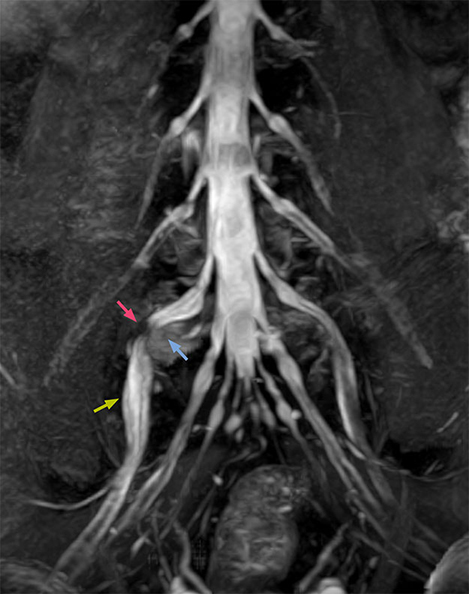

“In such case, we would then browse through axial T2-weighted MR images slice by slice and mentally reconstruct the actual situation based on both radiculography and MRI. Fortunately, NerveVIEW can now very well show nerve courses and presence of nerve compression or edema in one single image series.” “We have often seen NerveVIEW directly depict details of the nerve compression that were not observed by radiculography. Therefore, we think that with NerveVIEW we can reduce the number of invasive examinations, especially for some patients with lumbar plexus symptoms.”

“Although symptoms of typical disc herniation and atypical hernia are very similar, the actual site of herniation is different. It is therefore important to characterize the nerve’s condition both inside and outside of the intervertebral foramina. “Conversely, if we see no abnormality in NerveVIEW, we can assume at least that there is no severe condition that requires surgery. Like this, it can help us avoid unnecessary surgery. NerveVIEW can have a tremendous impact in this way.”

“NerveVIEW is really useful for those cases where a nerve disorder is strongly suspected based on the clinical examination but our regular MRI images do not show any findings. These atypical herniations and spinal canal stenosis, occurring in 5% to 15% of the total lumbar herniation/stenosis cases are our main target when using NerveVIEW,” says Dr. Yabuki.

“The intra-luminal signal of veins, especially around the intervertebral space, can be suppressed well with NerveVIEW. As a result, we can easily observe the detailed nerve structure around the posterior ganglion,” he says. “This is why we use 3D NerveVIEW for intraforaminal stenosis and extraforaminal stenosis/herniation (lateral disc herniation). On the other hand, if herniation is suspected to exist inside the dorsal root ganglion (DRG), balanced TFE or ProSet-FFE is applied. NerveVIEW is not suitable for evaluating the median type of herniation.” The SE-EPI DWI-based method for MR neurography works well for large FOV exams like whole-body MRI, but focal examination of nerves is often limited by the attainable spatial resolution (both inplane and slice direction) and geometric distortion. “3D NerveVIEW achieves higher in-plane resolution – close to our other routine spine sequences – and the source images can be used instead of adding a fat-suppressed T2-weighted sequence,” Tanji says.

“NerveVIEW can clearly show nerve courses and presence of nerve compression. However, when multiple abnormalities are seen, it can still be hard to determine which nerve is causing the symptoms,” says Dr. Yabuki. “In our experience so far, we see abnormal findings on NerveVIEW in about 70% of elderly patients. As the pain is usually caused by only one nerve, we thus need to find the exact corresponding nerve.” “With a nerve root block, the patient's pain is improved by infiltration of local anesthesia directly around the nerve root considered to be responsible. Knowing such nerve root block findings prior to image interpretation, helps to easily recognize abnormal findings on NerveVIEW as well. In other words, without a priori knowledge, based on symptoms and/or nerve root block findings, we must be aware of the possibility of overdiagnosis.”